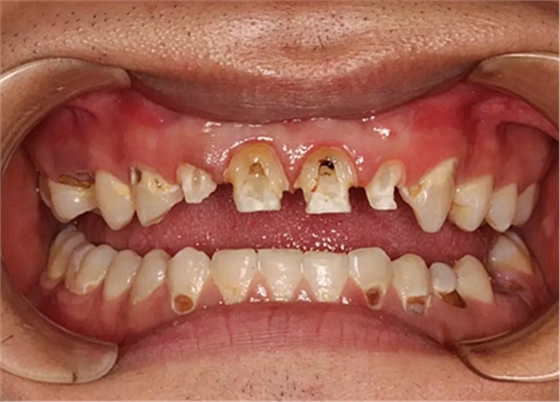

治療是從5月份開始的,醫(yī)生給我的主人驗(yàn)了血,做手術(shù)前的準(zhǔn)備,還給我們都用超聲波好好的都洗了個(gè)澡,把之前依附在我們身上的牙結(jié)石都沖了個(gè)干凈(齦上潔治術(shù))。治療先從我和其他3個(gè)兄弟開始。在麻藥的作用下,我們兄弟4個(gè)都被打開了身體,去除了已經(jīng)被蛀牙破壞的牙體,做了根管治療。

初次治療后

因?yàn)閷?duì)我們的治療需要分多次進(jìn)行,因此初次治療后做了臨時(shí)牙

第二次治療是半個(gè)月后,這次做了根管充填后將覆蓋在我們身體上的一部分牙齦切除,讓我們埋于牙齦下的身體暴露了一部分,也就是醫(yī)生說的冠延長(zhǎng)術(shù)。這是為了讓我們變得美觀一些。

根管治療

冠延長(zhǎng)術(shù)

兩周后,主人帶我們往醫(yī)院拆線,取模,比色,為我們重新量身定制了一套堅(jiān)固的“外套”。

第5次復(fù)診的時(shí)候,終于讓我們4個(gè)兄弟恢復(fù)了正常的容顏。

再來看看曾經(jīng)的我們